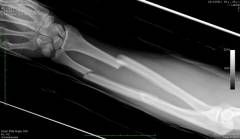

Рентгенография

Оценивает костную структуру предплечья, выявляет переломы и остеомиелит.

Перелом кости вызывает сильный болевой синдром и требует рентгенологического исследования.